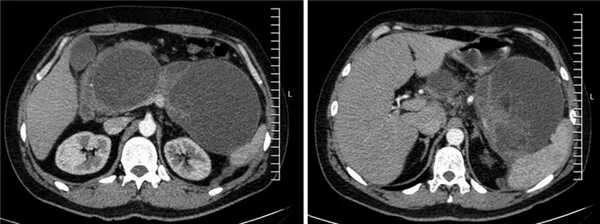

Мрт кисты поджелудочной